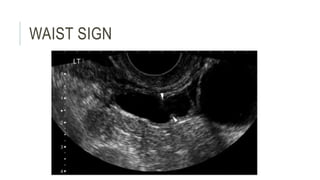

 (4) diametrically opposed indentations in the wall (“waist sign”) had the highest

likelihood ratio in discriminating hydrosalpinx from other adnexal masses

WAIST SIGN